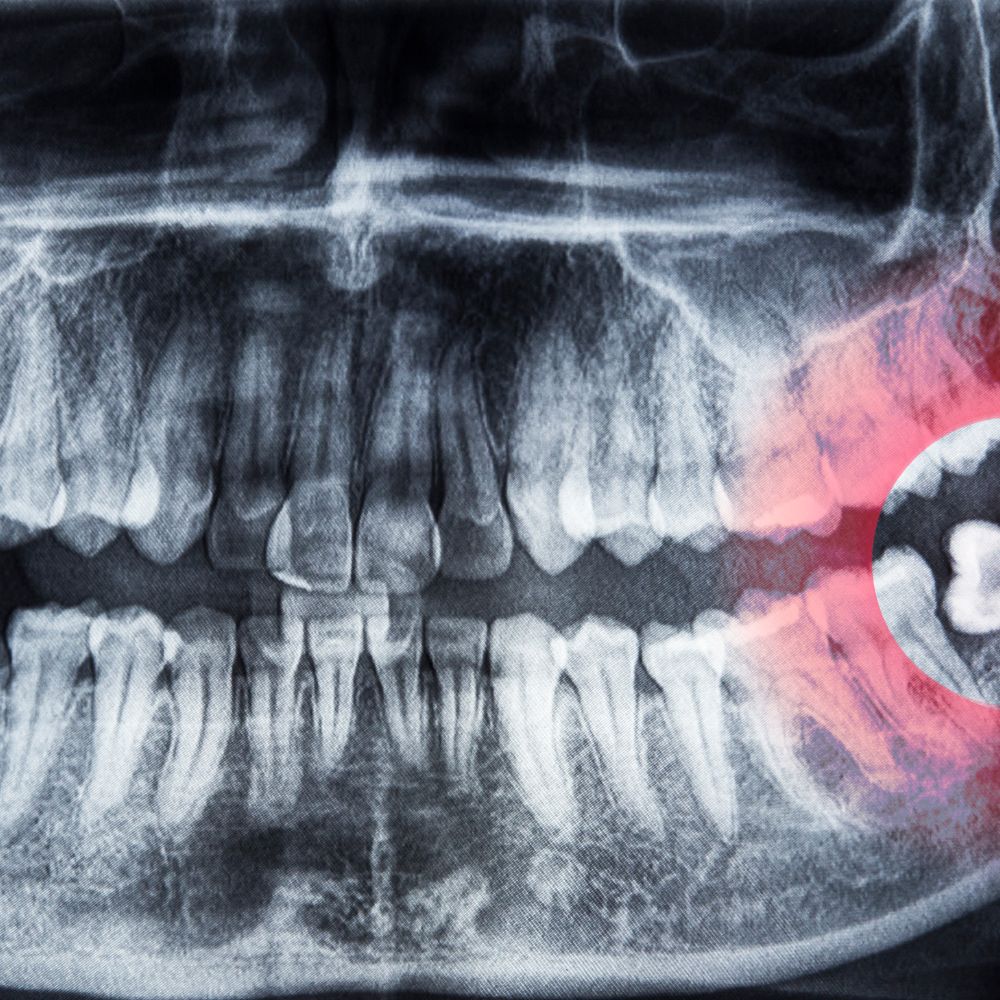

사랑니는 구강 내 맨 뒤쪽에 나오는 제3대구치로, 공간 부족, 비정상적 각도, 잇몸 염증, 인접치아 손상 등 다양한 문제를 유발할 수 있습니다.

특히 매복사랑니는 충치, 잇몸질환, 턱 통증, 얼굴 붓기 등 합병증 위험이 높아, 예방적 발치가 권장되는 경우가 많습니다.

- 전문의에게 시술받기, 사전 CT·파노라마 촬영